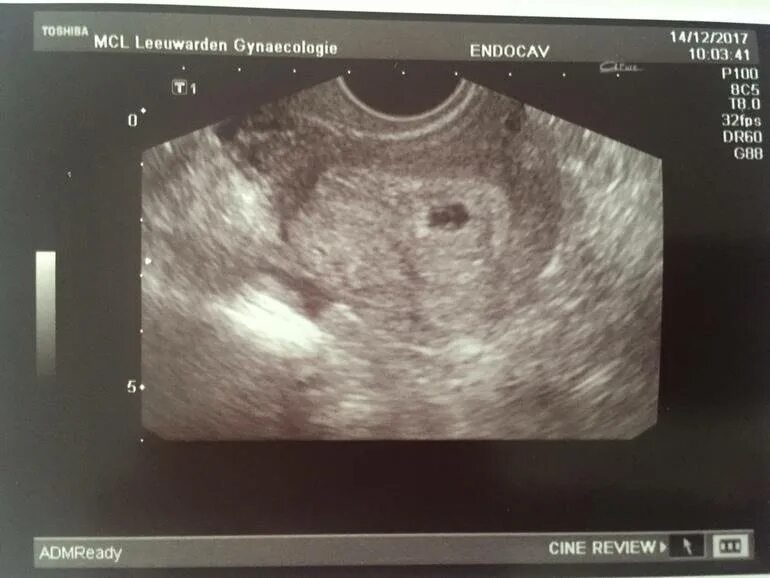

Как выглядит 5 дней беременности